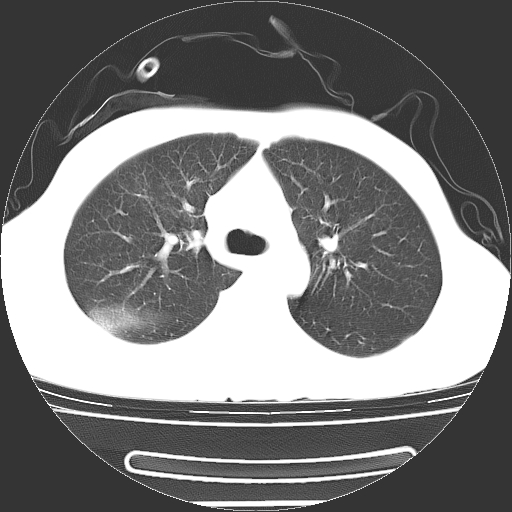

以下是引用dyqct在2008-4-29 8:43:00的发言:[br][br] 支持右侧胸腔包裹性积血。闭式引流管是不是插的太深了?

以下是引用zjzjr在2008-4-29 14:11:00的发言:[br]支持右侧胸腔包裹性积血。闭式引流管是不是插的太深了?胸腔引流,引流管快进入纵隔了.